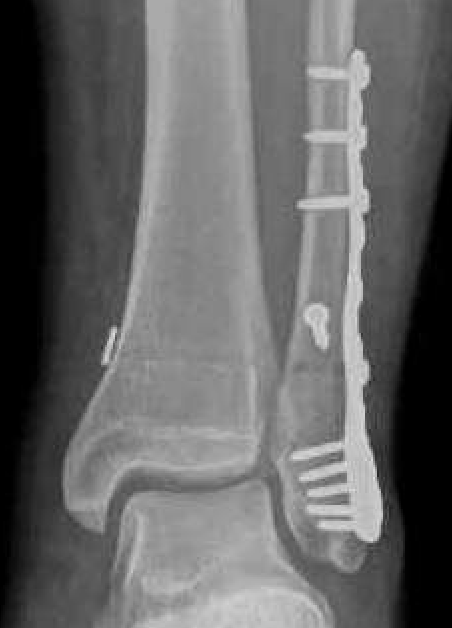

Unstable Weber B / torn deltoid ligament

Bimalleolar equivalent

Management

ORIF fibular

- ensure medial joint space fully reduced

- may need to open medial joint / removed osteochondral fragments / deltoid ligament

Open medial joint line after reduction

ORIF options

Plate - 1/3 tubular / DCP / anatomic locking plate

Fibular nail

ORIF